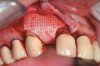

RegenerOss™ Allograft Putty (BIOMET 3i™, www.biomet3i.com) was molded to form the contours of the desired future ridge (Figure 3), and a 20-mm x 30-mm Ossix® Plus membrane (Colbar LifeScience, Ltd, Herzlya, Israel) was trimmed and adapted to cover the graft material (Figure 4). Periosteal relaxing incisions were made, and passive primary closure was obtained.

Figure 3  RegenerOss Allograft Putty molded to form the contours desired for the reconstructed ridge.

Figure 3

Figure 4  The Ossix Plus resorbable collagen membrane in place.

Figure 4